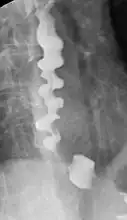

A barium swallow showing a corkscrew appearance due to distal esophageal spasm

Several radiographic findings are suggestive of DES, such as a "corkscrew esophagus" or "rosary bead esophagus" appearance on barium swallow x-ray, although these findings are not unique to DES.[4]